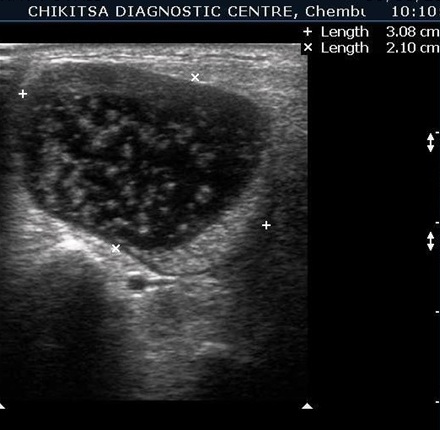

Salivary Gland Sonography

Salivary gland ultrasound is requisitioned by the doctor when there is swelling , pain or inflammation of a salivary gland.

Calculi may develop in the salivary gland ducts. Rarely, tumors may develop in salivary glands.